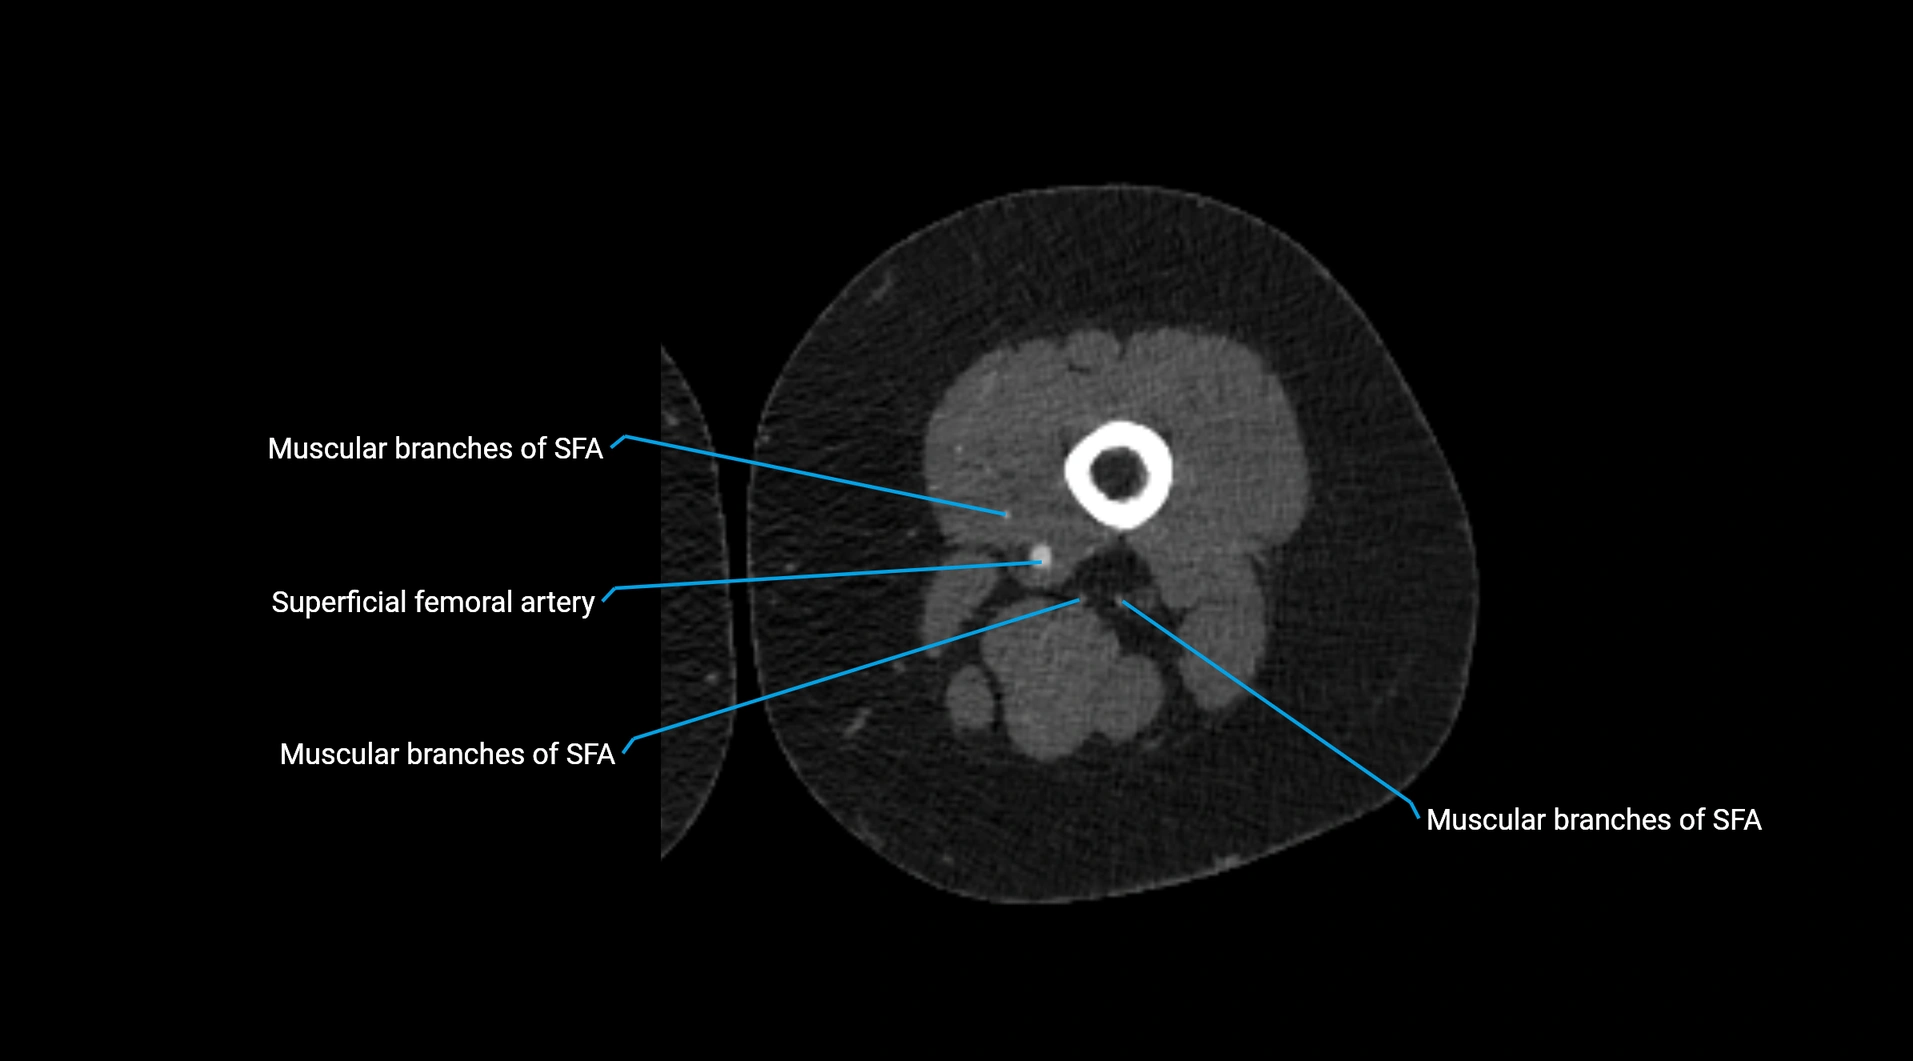

Contrast-enhanced CT (CTA):

• Gold standard for abdominal aortic imaging

• Provides excellent detail of lumen, wall, aneurysm, thrombus, and branch vessels

• Multiplanar and 3D reconstructions help in aneurysm measurement, stent graft planning, and dissection evaluation

• Detects acute rupture, traumatic injury, or occlusion with high sensitivity